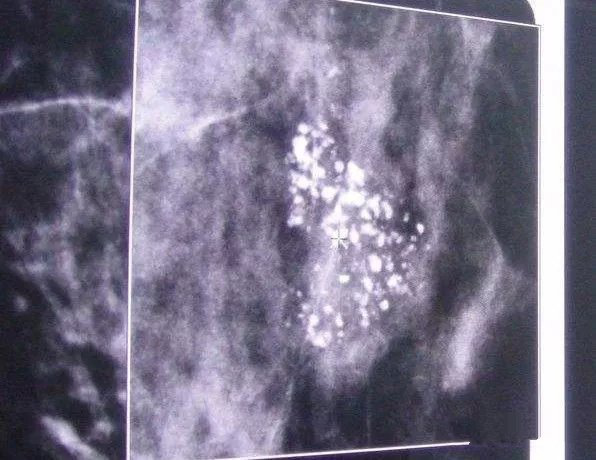

乳腺钙化灶 精准切除后一验竞然是癌元凶

1080x592 - 76KB - JPEG